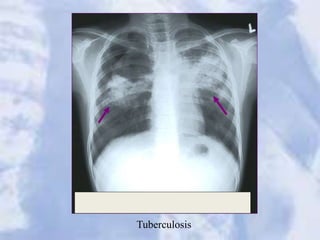

Tuberculosis